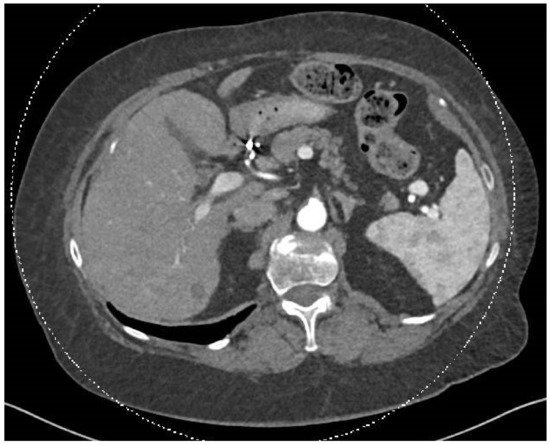

A post-SIRT treatment follow-up PET-CT scan in April 2024 showed no pathological uptake. The previously identified hypervascular liver lesions were absent, and new, ill-defined hypodense changes were observed in both liver lobes, primarily on the right, potentially representing post-SIRT changes (Figure 3). The interventional radiologist and diagnostic radiologist team reviewed the findings. They confirmed that these changes were consistent with expected post-treatment effects, indicating an excellent response, with the lesions now appearing as cystic cavities.

Figure 3.

In this CT scan, dated 30 July 2024, of the chest, abdomen, and pelvis, performed after intravenous contrast injection with additional oral contrast administration, pre- and post-contrast imaging was conducted using a triphasic protocol focused on the liver. Comparison was made with the previous CT examination from 15 May 2024. The smaller lesions disappeared following SIRT treatment, and the dominant lesion has become hypodense, indicating an inactive metastasis.